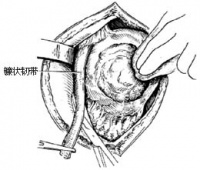

小网膜、胃后壁和腹后壁腹膜之间的扁窄间隙叫做网膜囊omentalbursa(又称Winslow’s囊)。囊的前壁由上向下依次为小网膜、胃后壁和胃结肠韧带;后壁是覆盖于胰、左肾和左肾上腺前方的腹后壁腹膜,下方还有横结肠及其系膜;上壁为膈下面的腹膜和肝尾叶;下壁为大网膜前两层与后两层的愈合部;左壁为脾、胃脾韧带、脾肾韧带和脾膈韧带;右侧借网膜孔与大腹膜腔相通。

网膜孔omentalforamen(又称Winslow’s孔)上界为肝尾叶,下界为十二指肠的上部起始段(球部),前界为肝十二指肠韧带的游离缘,后界为覆盖下腔静脉的腹后壁腹膜。网膜孔一般仅可通过1-2个手指。

网膜囊的结构和毗邻特点在医疗实践中具有重要意义。如胃溃疡胃后壁穿孔时内容物常局限于网膜囊内,形成上腹部局限性腹膜炎,继之常引起粘连,如胃后壁与横结肠系膜或与胰腺粘连,从而增加了胃手术的复杂性。胃后壁、胰腺疾患或网膜囊积液时均须进行网膜囊探查,一般采取切开胃结肠韧带的入路,但由于邻近器官的炎性病变粘连,胃结肠韧带与其深面的横结肠系膜可发生粘连,在切开胃结肠韧带时应予特别注意。

沿胃大弯下方约2厘米处,剪开大网膜前2层,将右手食指由切口伸入胃后面的网膜囊,在胃底部和脾门之间,用拇指和食指夹撮胃脾韧带,再用左手沿脾与膈之间向绕过脾后缘,与右手食指间探查脾肾韧带。在脾的下方可见从结肠左曲连于膈的膈结肠韧带。

4.探查网膜囊和网膜孔

将右手食指自胃大弯下缘的切口伸入网膜囊,依次探查囊的上壁为肝左叶和膈下面的腹膜,下壁即大弯切口处、大网膜前两层和后两层的愈着部,左界为胃脾韧带和脾肾韧带,右界为小网膜游离右缘后方的网膜孔。再将左手食指伸入网膜孔,使左、右食指在网膜囊内会合,证实网膜孔为网膜囊右侧的开口。摸触网膜孔的四界,前界为小网膜(肝十二指肠韧带)的游离右缘;后界为覆盖下腔静脉的腹后壁

腹膜;上界为肝尾叶;下界为十二指肠上部。